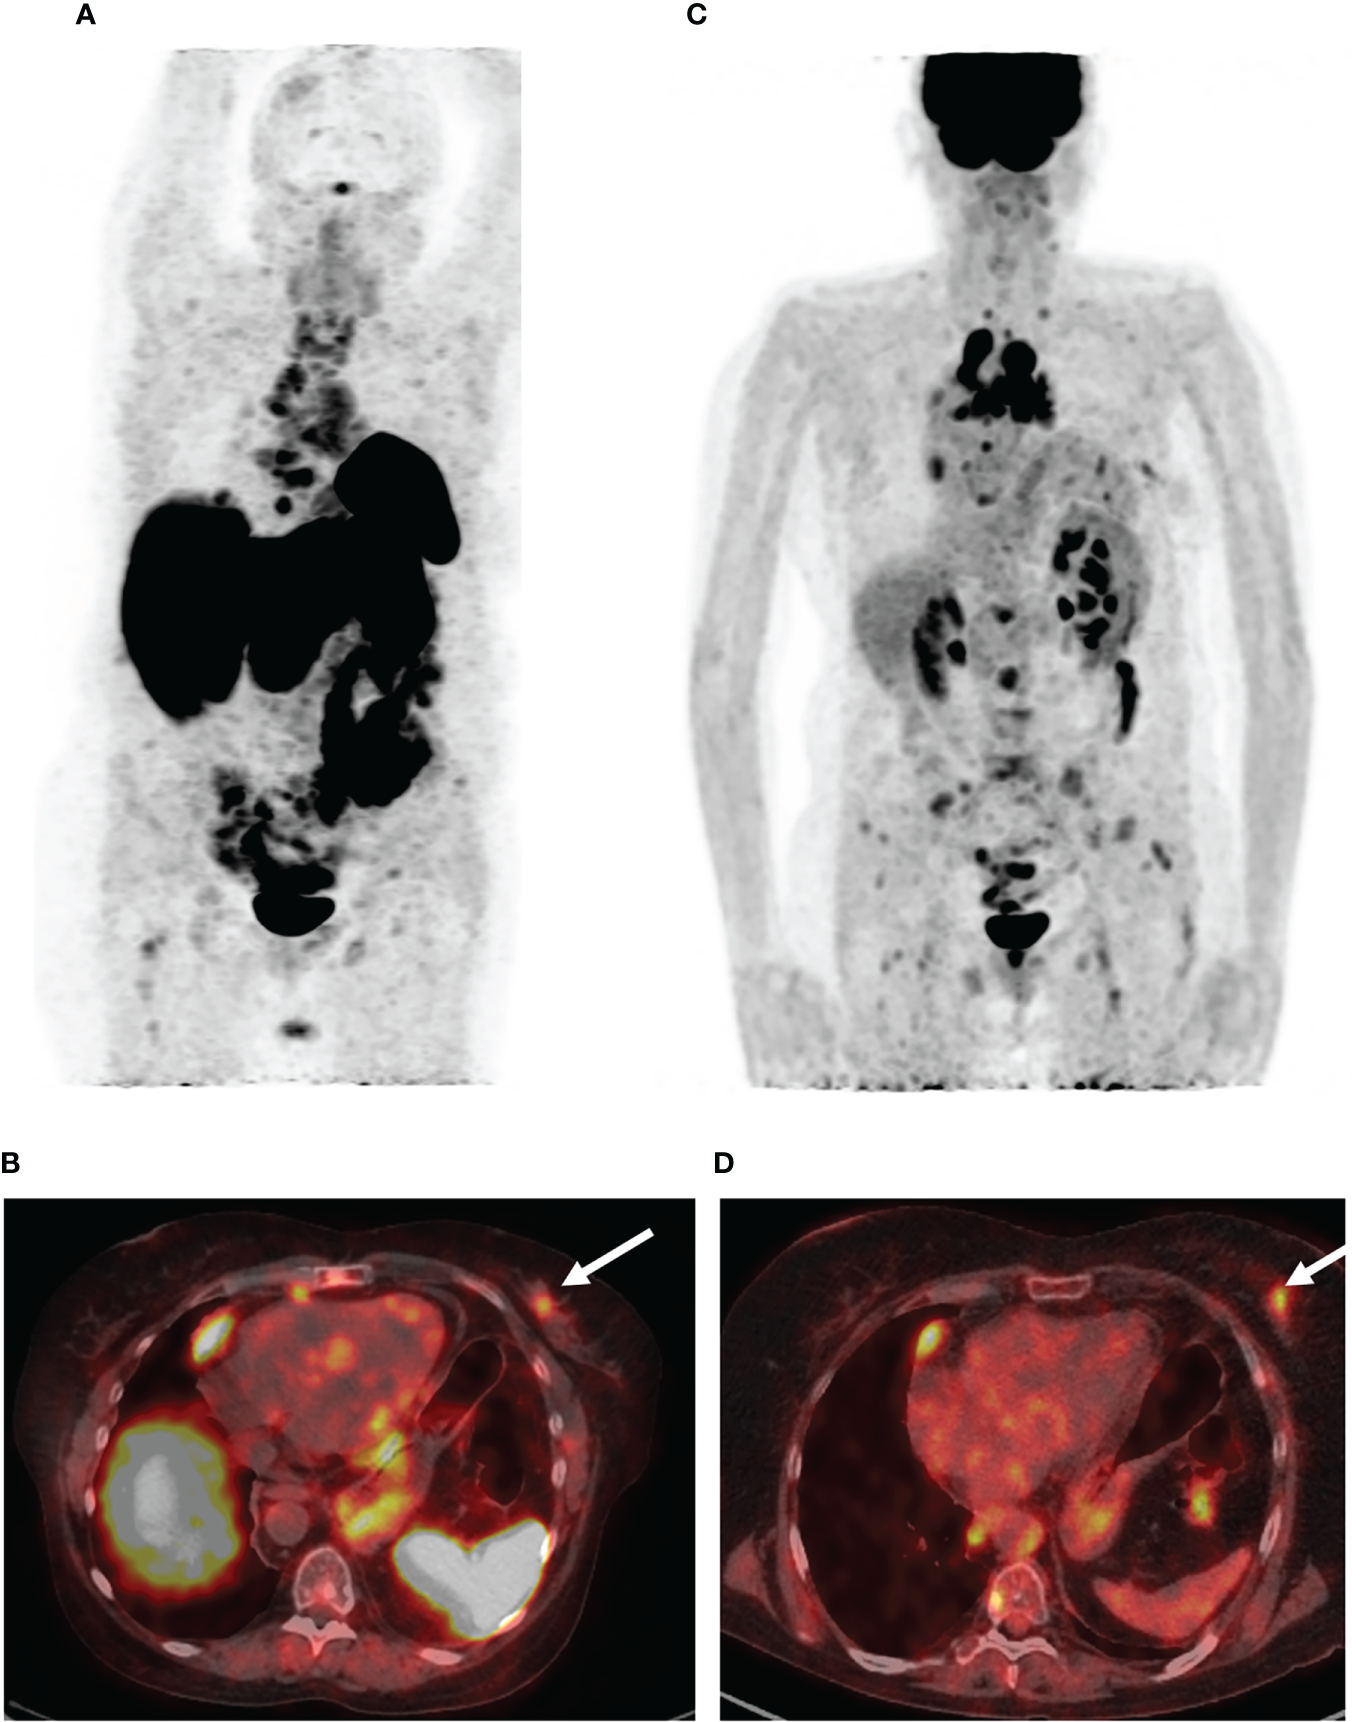

Five months after the surgical treatment, the patient underwent [68Ga]-DOTA-TATE PET/CT scan to assess the efficacy of the pharmacological treatment. This showed an increase in the size of the previously detected metastases and the appearance of a new mediastinal lymph node and bone metastases, while the radiopharmaceutical uptake did not have a significantly effect (Figure 3A). A month before the first admission to the endocrinology department, mammography was performed, which showed only fibrocystic breast disease with a BI-RADS score of 2. However, the follow-up [68Ga]-DOTATATE PET/CT scan now showed an avid metastatic lesion in the upper inner quadrant of the left breast (Figure 3B) that was not visualized during the previous PET/CT scans. An [18F]-FDG PET/CT scan showed intense tracer uptake in the same area as the [68Ga]-DOTA-TATE PET/CT scan, indicating left breast metastasis of the ovarian NET (Figures 3C, D). Ultrasound imaging identified a 2.2 × 1.1-cm hypoechoic mass with irregular contours and vascularization as shown by color Doppler sonography. An ultrasound-guided 18-G needle core biopsy was performed and the histological evaluation showed a neuroendocrine tumor of nests and tubules with “salt and pepper” nuclei. Immunocytochemistry showed the expression of chromogranin A, synaptophysin, NSE, and ACTH, and the Ki-67 index was 15% (Figure 4). The majority of the tumor cells expressed the somatostatin receptor 5 subtype (Figure 4E). These findings were similar to the immunocytochemistry of the previous metastases and the primary neuroendocrine tumor of the ovary.

Figure 3

PET/CT images with [68Ga]-DOTA-TATE and [18F]-FDG. (A) The maximum intensity projection (MIP) images summarize the physiological and pathological distribution of [68Ga]-DOTA-TATE in the body. PET/CT scan showed an increase in the size of the previously detected metastases and the appearance of a new mediastinal lymph node and bone metastases. (B) [68Ga]-DOTA-TATE. PET/CT revealed an avid metastatic lesion in the upper inner quadrant of the left breast (white arrow). (C) The MIP images of [18F]-FDG PET showed intense tracer uptake in the same area as the [68Ga]-DOTA-TATE PET/CT scan. (D) [18F]-FDG-positive metastatic lesion in the left breast (white arrow).